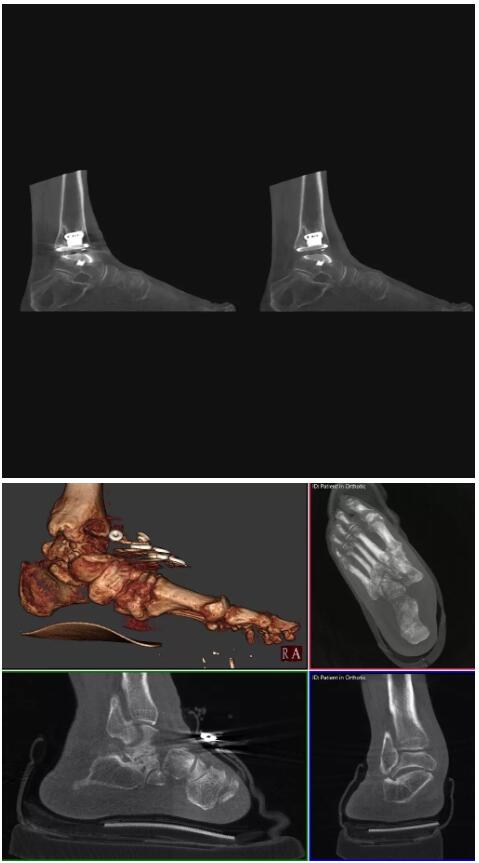

以上介紹的CT均來自國外同一家公司,這些CT均配置了可視化軟件,可以進行切片、3D重建以及大型CT附帶的所有典型的操作功能。

當然,這類充滿想象力的CT,國內(nèi)也有生產(chǎn)廠家在研究,比如賽諾威盛研發(fā)的InsitumCT Zero,可以很好的適應特殊的臨床應用場景,超大孔徑多種自由度組合,可實現(xiàn)水平和垂直等多種掃描模式。

對于急診外傷患者,它縮短了診斷到治療的路徑,避免移動患者帶來的二次損傷;復合手術室中,它可以讓醫(yī)生第一時間確認或調(diào)整手術方案,大大縮短手術時間;對于需要放療定位、質(zhì)子治療的患者,一站式的定位、治療服務能夠更加精準。

以下是這些“特立獨行”的CT所拍出來的圖像: